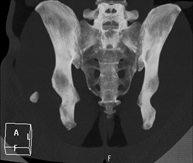

Sacroiliac CT

Radiological examination based on an X-ray system and detectors that rotate around the patient, reconstructing the images by computer (multidetector computed tomography - MDCT) to study the sacroiliac joints and rule out inflammatory, traumatic or degenerative diseases.